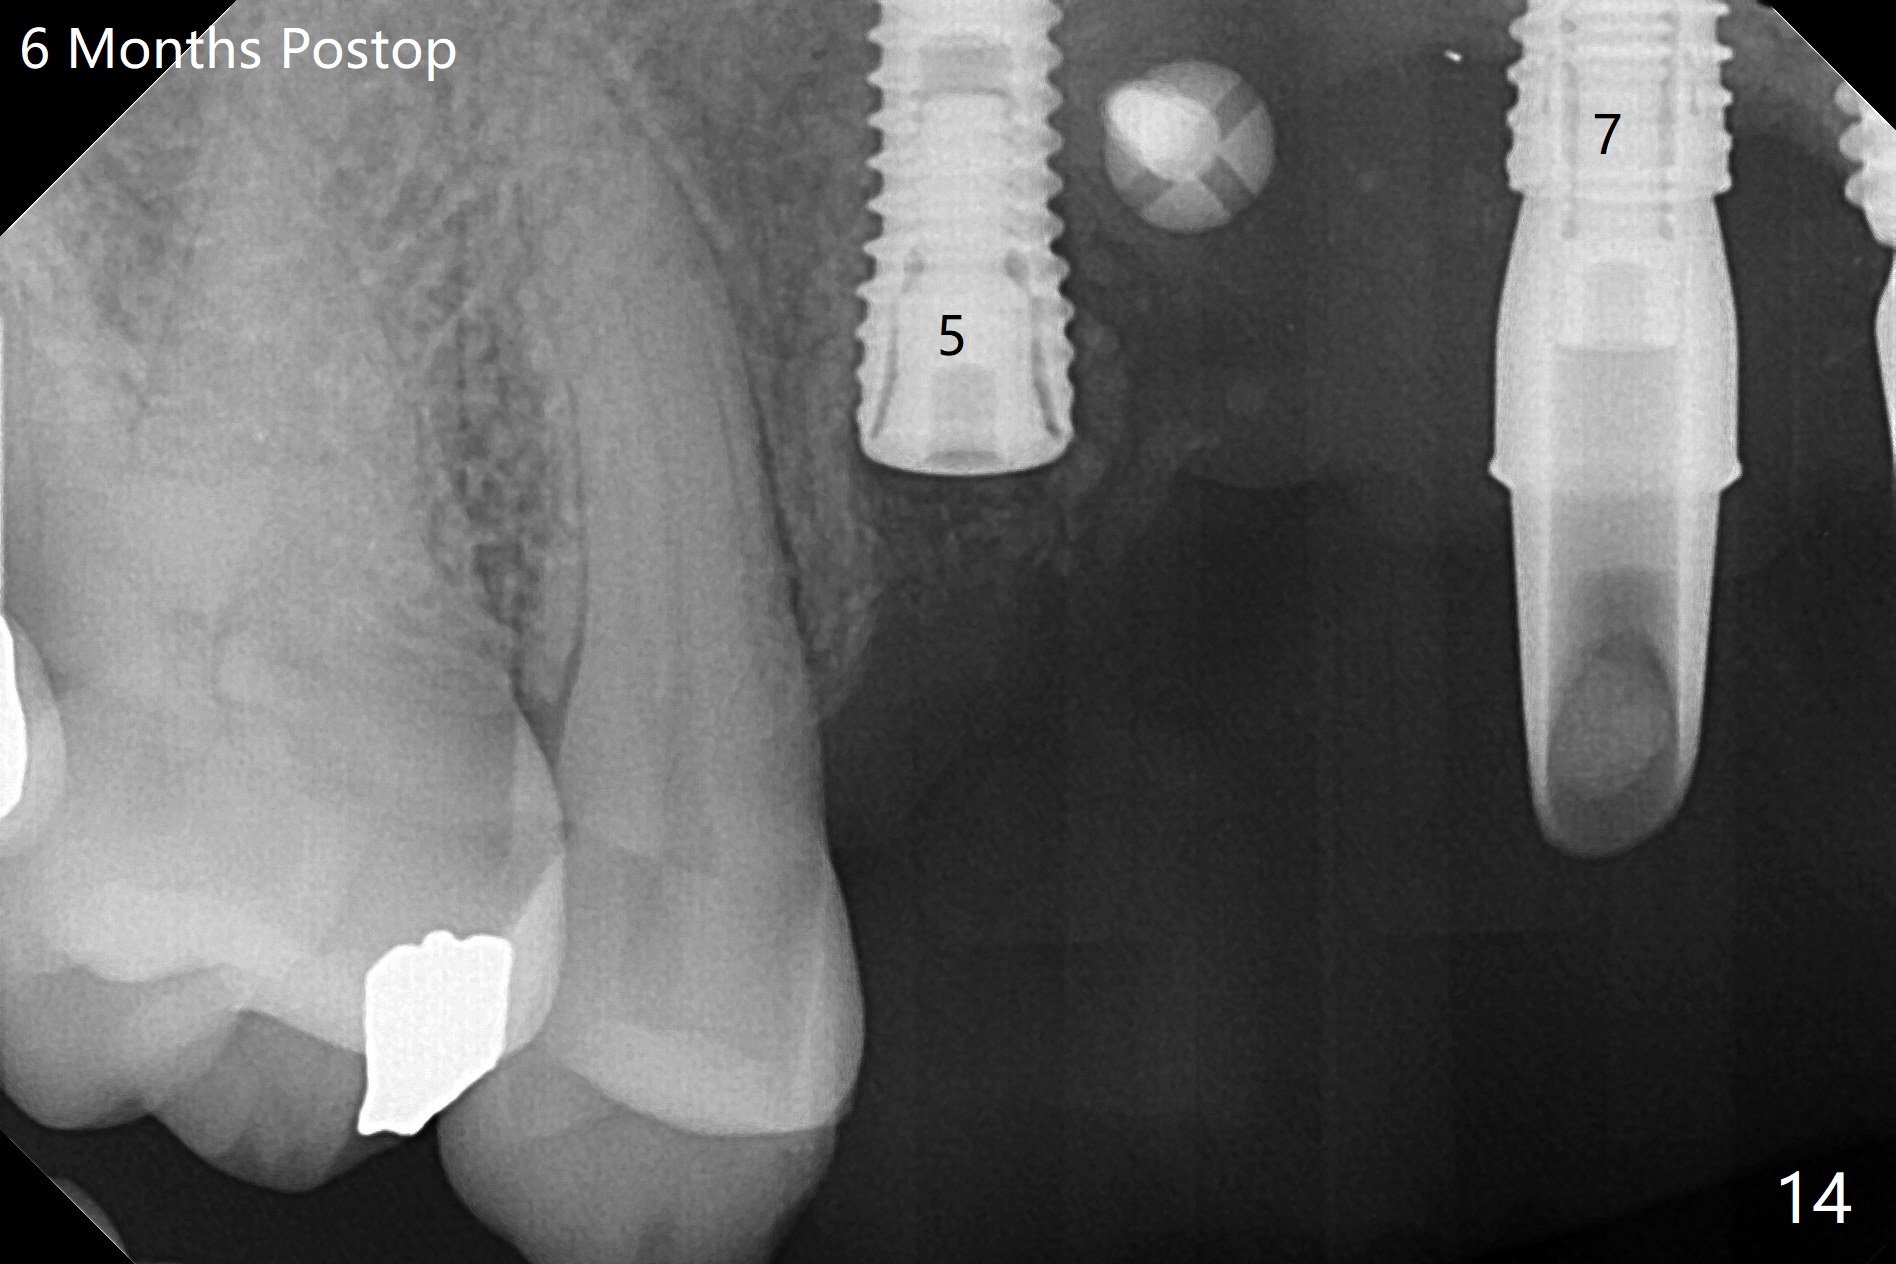

在6,7号牙位牙槽嵴切口,翻瓣,找不到上次放置的tenting screw,不过7号牙位骨质虽然低,够宽的,开始钻洞(图四),植入3.8乘8.5毫米植体,扭力足够(图五),近中舌侧暴露螺纹堆加骨粉(图五*),然后放置基台,再次在后者周围放置骨粉(图五至七),覆盖两张PRF膜后缝合(图八),最后在三个箭头周围放置牙周敷料。术后CT显示植体与tenting screws(图九,十箭头)有一定距离,但是5号牙植体颊侧根尖穿孔(图九 *)。如果植体不脱落,需做侧方切口植骨。术后七天7号植体腭侧肿胀(图十一 *),切开没有脓水,插入牙胶尖,它末端指向7号植体周围tenting screw。后者可能需要拔除,同时5号牙颊侧根尖植骨,但是为时太早,可能打搅骨粉生长。术后两周腭侧肿胀没有消失,但是不痛,继续观察。术后接近6个月,软组织正常(图十三),但是5,7植体周围没有骨质(图十四,五)。由于近中tenting screws周围软组织触痛(局麻不全情况下),螺钉取出(图十六,七(*)),而远中螺钉好像有帮助5植体螺纹骨粉撑起,所以留下(腭侧穿孔部分去除),最后放置粘性骨粉(图十八:*)和PRF膜(两张由7基台打孔固定)。